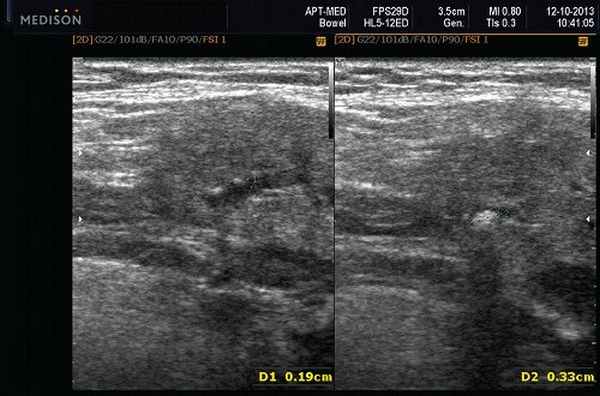

- обструктивные сиаладениты, развивающиеся при затруднении оттока слюны при обструкции выводного протока камнем (рис. 5-7) или сгустившимся секретом, а также вследствие рубцового стеноза протока. По распространенности процесса различают очаговый, диффузный сиаладениты и сиалодохит - воспаление выводного протока. Течение процесса может быть острым и хроническим;

Рис. 5. Камень протока поднижнечелюстной слюнной железы.

Рис. 6. Камень в паренхиме поднижнечелюстной слюнной железы.

Рис. 7. Камень в протоке поднижнечелюстной слюнной железы.